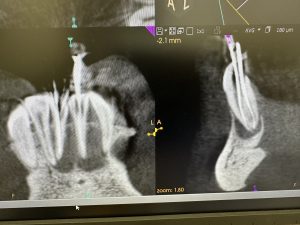

次は、歯性上顎洞炎の根管治療2カ月後

だいぶ回復💪